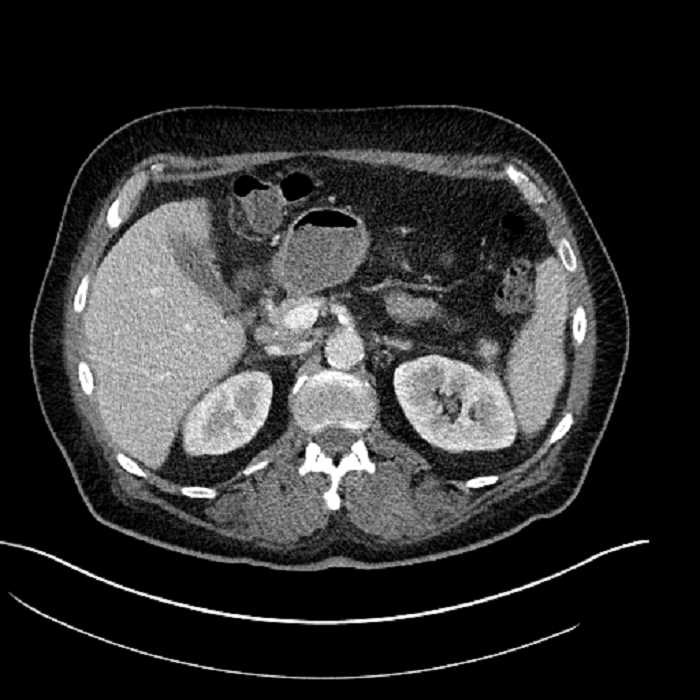

• Large fluid density structure in hepatic segments 7 and 8 measuring 10 x 7 x 7 cm with internal septation and circumferential ill-defined low density compatible with edema

• Clearly marginated fluid density structure in segment 7 and several other scattered tiny hypodensities, which likely represent cysts

• The classic CT imaging appearance is a double target sign with internal low density surrounded by an internal enhancing rim (capsule) and a low density external rim (edema)

• Abscesses may be unilocular or multilocular

• Gas is present in a minority of cases

Hepatic abscess showing the double target sign with low density internally surrounded by a thin inner enhancing rim (red arrow) and ill-defined outer low density rim (yellow arrow). Blue arrow indicates an internal septation. Red arrows: additional smaller subcapsular abscesses. Red arrow: focal contained perforation associated with diverticulitis.